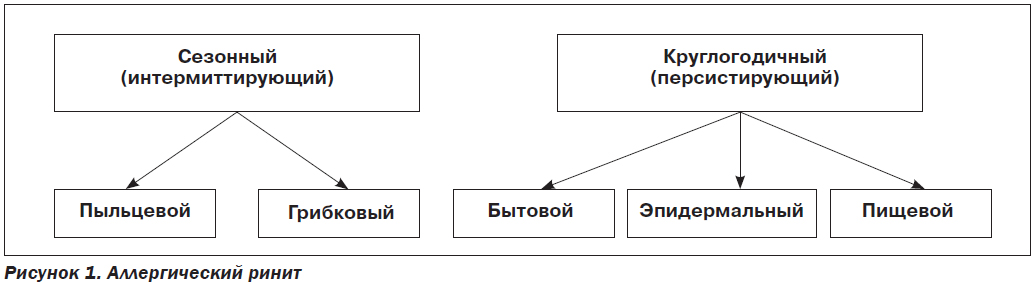

Европейская академия аллергологии и клинической иммунологии приняла свою версию Международного консенсуса в лечении АР. Сезонный АР предлагают именовать интермиттирующим АР, а круглогодичный АР — персистирующим АР.

Аллергодерматозы сопровождают различные АЗ. У 60 % больных аллергическим ринитом (АР делится на сезонный и круглогодичный; бытовой, эпидермальный, грибковый) в 40 % случаев возникает аллергическая крапивница, а в 20 % — атопический дерматит (АД) [4, 5].

Сезонный (интермиттирующий) аллергический ринит (САР) или поллиноз. САР — это аллергическое заболевание слизистой оболочки носа, которое –обусловлено гиперчувствительностью к аэрозольным АГ (из пыльцы растений, спор грибов), концентрация которых в воздухе периодически становится причинно-значимой.